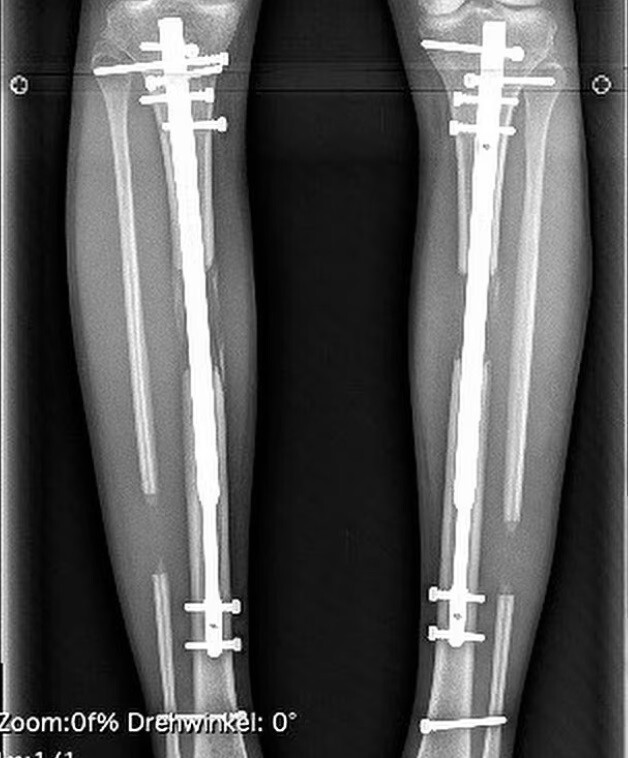

Fischer first went under the surgeon's knife at the age of 24, then She has grown 8 inches. The doctors inserted adjustable telescopic rods and gradually twisted them, thereby lengthening legs.

In an interview with the German newspaper Bild, she spoke about the process operations: "The bones of the lower leg are broken completely, the needles are inserted and the external fixation device. You stretch your shins yourself, tightening the nuts. Ten clicks a day on each side give additional 0.5 mm".